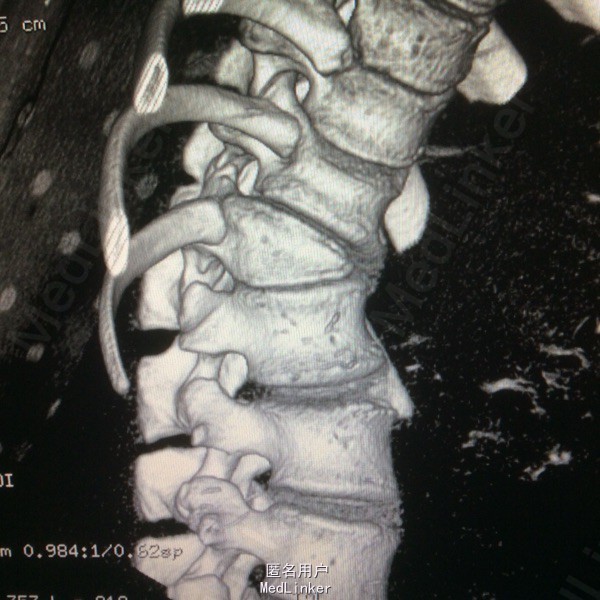

患者呈向心性肥胖,眼角略上斜,下颌小,上下牙间距大,闭齿音发音不清,性早熟,外阴幼稚,大小阴唇发育不良,手脚小胖,指端纤细,余查体无明显异常。 辅助检查:胸9-10胸12-腰1椎体融合、胸11呈半椎体,椎管内脊髓未见明显信号异常.

胸椎半椎体畸形 左侧第10肋骨缺如 隐形骶椎裂 双下肢膝外翻 双下肢肌挛缩症 脊柱畸形术,胸5、6、8、9腰1-2-3双侧椎弓根螺钉,去除胸11-12后方椎板,胸12半椎体及上下间隙间盘去除,椎间隙植骨。